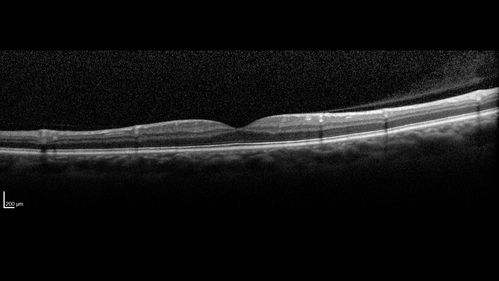

Normal Left eye

Left eye of patient with valsalva retinopathy in the right